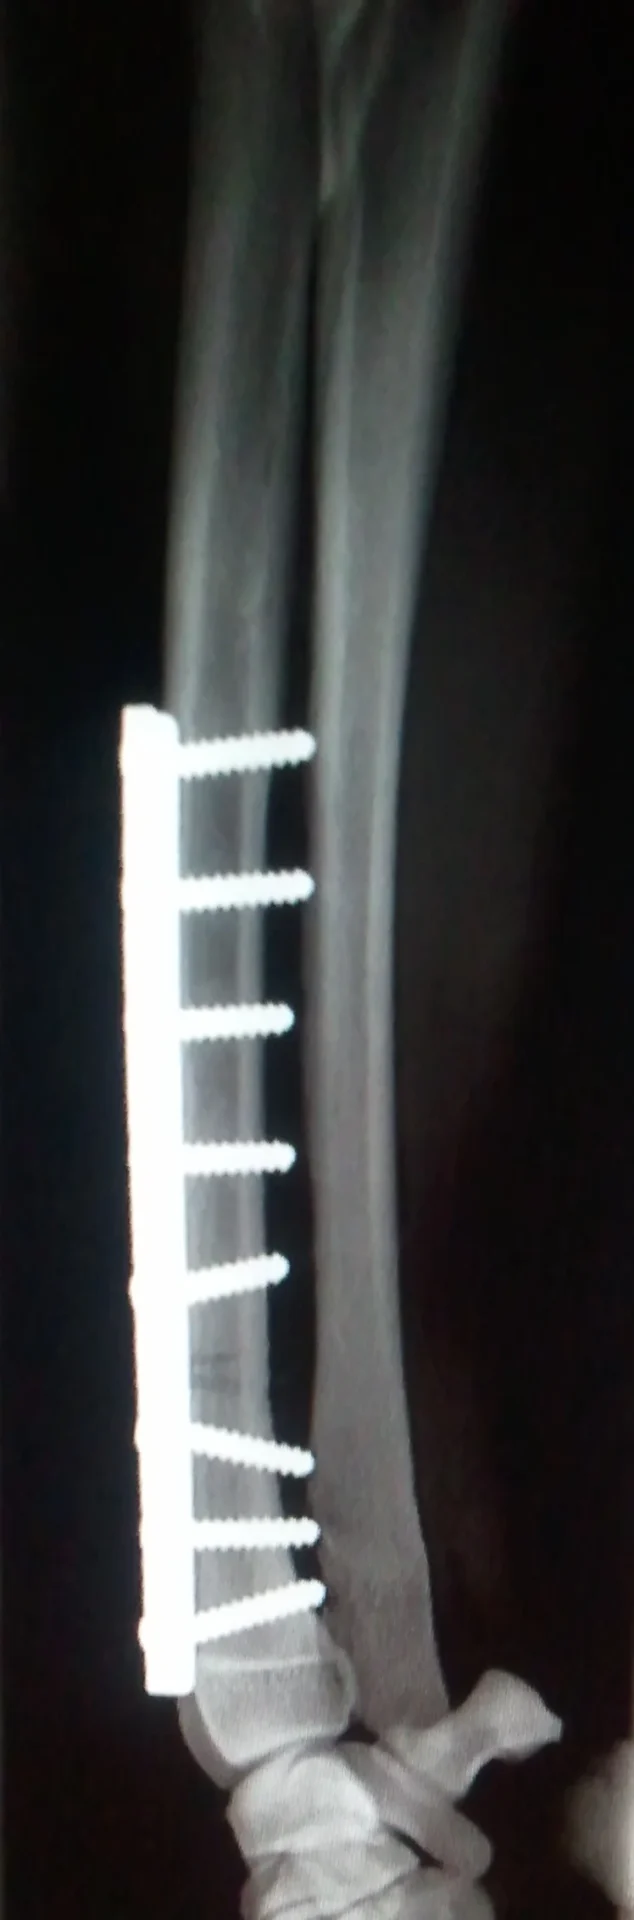

Galería de casos clínicos

Casos clínicos de cirugía (tejidos blandos, traumatología, neurocirugía, artroscopia)